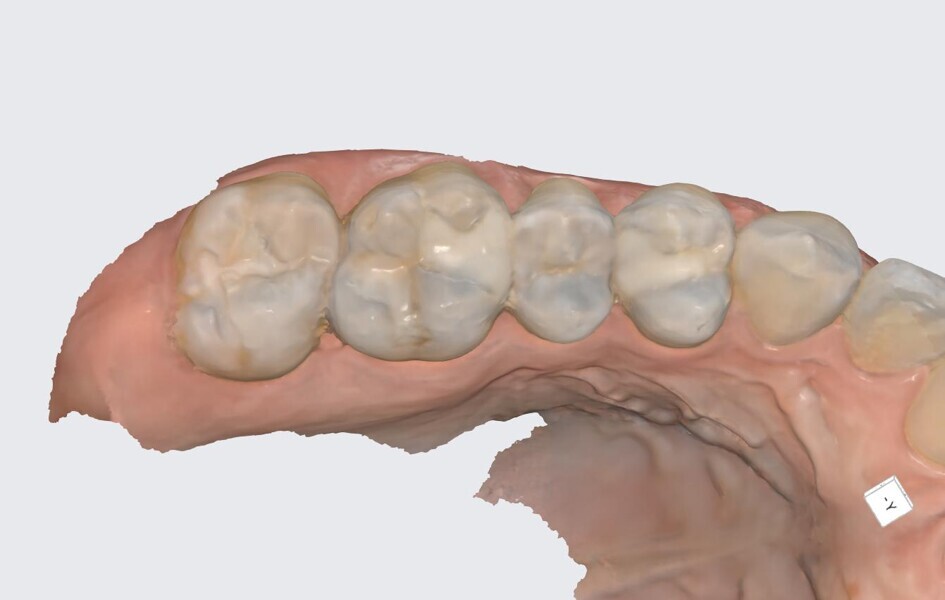

Fig. 21: Pre-op scan of the maxillary right posterior sextant.

The prepared sextant and opposing dentition as well as the occluded arches were scanned with the Medit i900 and the scans imported into Medit ClinicCAD. The restorations were designed in the software with a cement gap of 0.1 mm and a minimum thickness of 0.6 mm to contours matching the preoperative treatment scan (Fig. 23). The virtual restorations were removed from the virtual models in preparation for 3D printing on the Midas printer (Fig. 24). Supports were added to the virtual onlays and the designs prepared for 3D printing.

The patient was anesthetised with local anaesthetic. A preoperative scan of the arch was performed with a Medit i900 scanner to aid in the virtual design of the planned restorations (Fig. 21). The old composite was removed along with the caries with a high-speed handpiece and appropriate burs. Caries detector dye (Caries Finder) was used to ensure complete caries removal. The preparations were refined by performing occlusal reduction of 1.5 mm, and it was confirmed that the margins of the onlays did not extend into functional occlusal contact areas when the patient occluded (Fig. 22).